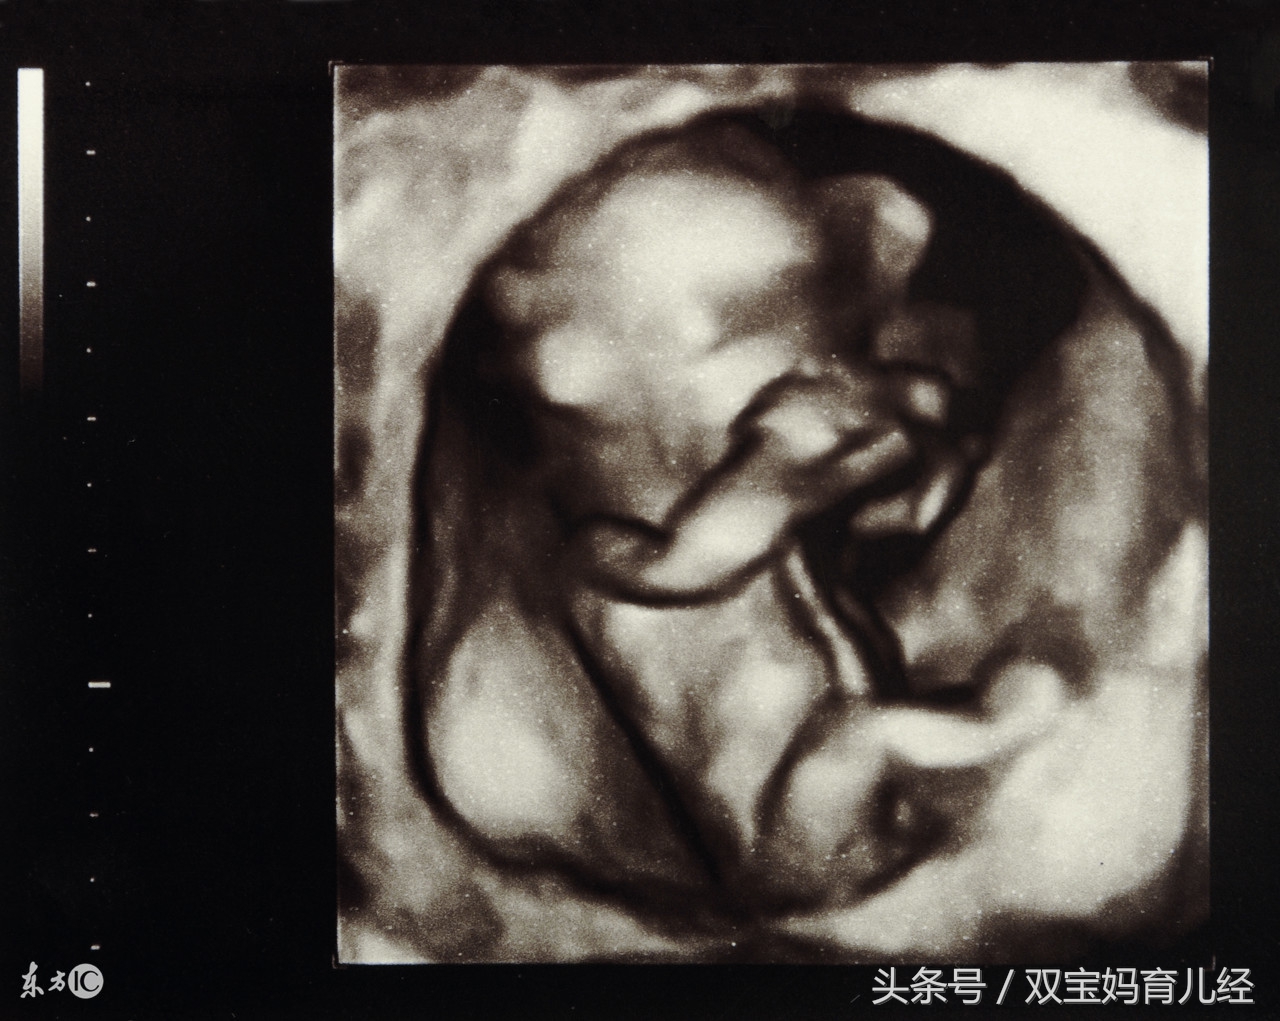

到了医院,医生马上安排了B超检查,惊奇地发现肚子里的宝宝一只脚已经伸到了子宫外!孕周增大,肚子里的宝宝活动太频繁,一脚把玲姐的子宫给踢破了!

医生解释,因为玲姐第一胎是剖腹产,子宫动过手术,属于疤痕子宫.在疤痕没有完全愈合的情况下,又匆匆忙忙怀上了第二胎,子宫根本没有得到休息, 到了孕晚期,就容易发生宝宝在肚子里面施展不开,踢破妈妈子宫,导致子宫破裂的情况.